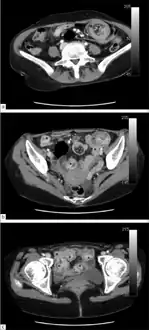

An intussuception as seen on CT

An intussusception is often suspected based on history and physical exam, including observation of Dance's sign. A digital rectal examination is particularly helpful in children, as part of the intussusceptum may be felt by the finger. A definite diagnosis often requires confirmation by diagnostic imaging modalities. Ultrasound is the imaging modality of choice for diagnosis and exclusion of intussusception, due to its high accuracy and lack of radiation. The appearance of target sign (also called "doughnut sign" on a sonograph, usually around 3 cm in diameter, confirms the diagnosis. The image seen on transverse sonography or computed tomography is that of a doughnut shape, created by the hyperechoic central core of bowel and mesentery surrounded by the hypoechoic outer edematous bowel.[8] In longitudinal imaging, intussusception resembles a sandwich.[8] It is also called "pseudokidney" sign because hyperechoic tubular centre is covered by a hypoechoic rim producing a kidney-like appearance.[9]